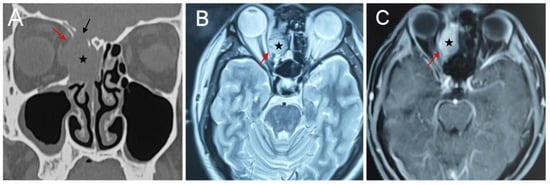

Objectives: We aimed to characterize the clinicopathologic features, treatment, and outcomes of three types of Switch/Sucrose Nonfermentable (SWI/SNF)-deficient sinonasal carcinomas (SDSCs), thereby expanding the spectrum of these rare entities and facilitating early diagnosis. Methods: We designed a retrospective single-center case series to analyze the clinicopathological features of 17 patients with SMARCB1-deficient sinonasal carcinoma (n = 10), SMARCA4-deficient carcinoma (n = 6) and SMARCA4-deficient sinonasal teratocarcinosarcoma (TCS) (n = 1) treated between 2018 and 2025, and reviewed the relevant literature. Results: The cohort included 14 males and 3 females, aged 26 to 69 years (mean, 47 years). SMARCB1-deficient sinonasal carcinomas predominantly involved the ethmoid sinus (6 of 8 patients), presenting epistaxis (7 of 10 patients), nasal obstruction (5 of 10 patients), and ocular symptoms (4 of 10 patients). SMARCA4-deficient sinonasal carcinomas mainly arose in the nasal cavity (3 of 4 patients), characterized by nasal obstruction (4 of 6 patients), and epistaxis or purulent rhinorrhea (4 of 6 patients); ocular symptoms were less common (2 of 6 patients). The TCS patient had left nasal cavity and ethmoid involvement with nasal obstruction and purulent rhinorrhea. Most patients presented with advanced-stage disease (T4a, n = 9), with skull base (n = 6), and orbital (n = 3) involvement. Histologically, immunohistochemical analysis confirmed complete SMARCB1 or SMARCA4 loss (complete in carcinomas and partial in TCS), diffuse CK positivity, and high Ki-67 indices. Treatment modalities included: chemotherapy and immunotherapy without surgery (n = 2), radical surgery with adjuvant chemoradiotherapy and immunotherapy (n = 2), radical surgery with chemoradiotherapy (n = 9), postoperative radiotherapy alone (n = 3), and non-radical surgery with chemoradiotherapy (n = 1). At a median follow-up of 19 months (range, 8–57 months), 2 patients were lost to follow-up, 3 died, 2 had persistent disease, and 10 remained disease-free. Conclusions: SDSC is an aggressive tumor with male predominance and advanced-stage presentation. Early recognition and appropriate immunohistochemical evaluation are essential for timely diagnosis and management. Prospective studies of novel targeted and immunotherapeutic strategies are warranted. Full article

Figure 1